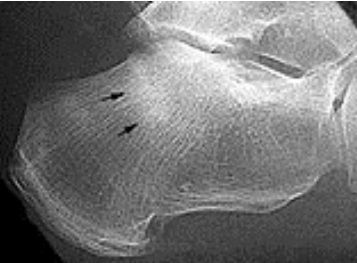

| What disease is this? What do the arrows indicate? | Gout Arrows = 'punched out' erosions |